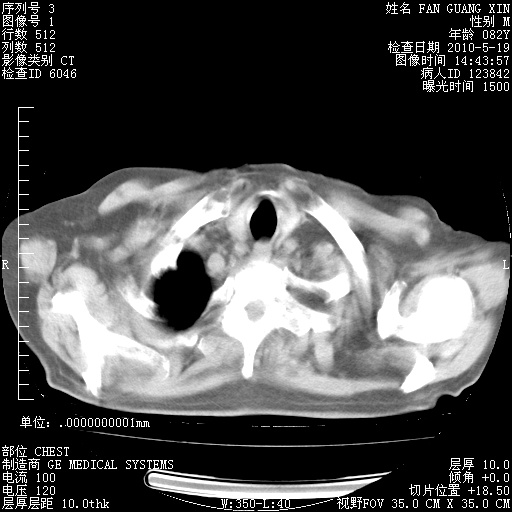

可改为口服强的松40-50mg/d治疗,若病情仍稳定,胸部阴影不再吸收可逐渐减量